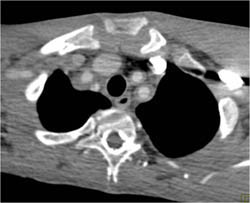

Takayasu's Arteritis